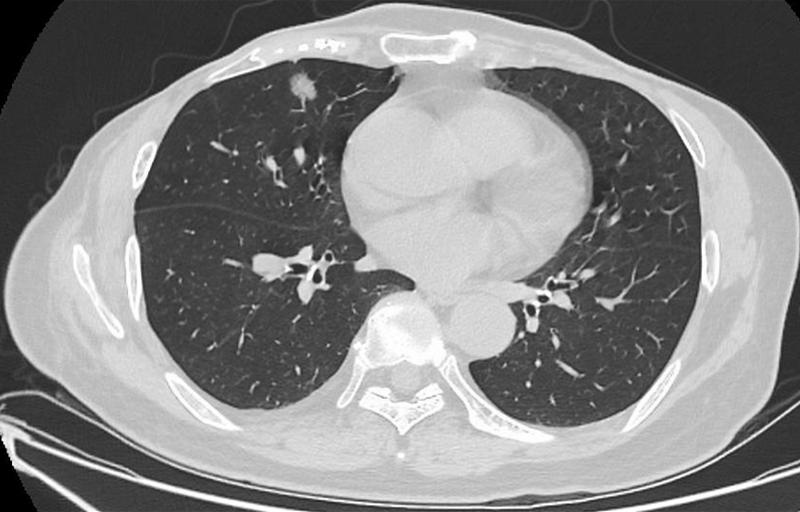

肺結(jié)節(jié)是指肺部出現(xiàn)的直徑小于3厘米的圓形或類圓形病灶,大多數(shù)肺結(jié)節(jié)是良性的,但部分可能需要治療,肺結(jié)節(jié)的癥狀因個(gè)體差異而異,部分患者在早期可能無(wú)任何癥狀,因此定期進(jìn)行體檢至關(guān)重要。